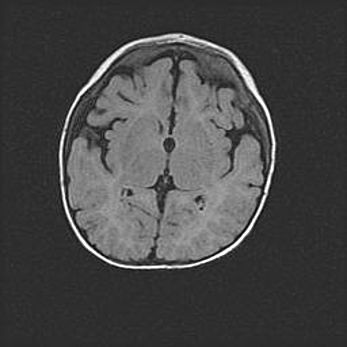

Наружная гидроцефалия с возможной атрофией височных областей.

Возраст: 28 дней

Вес: 3670 г

Пол: мужской

Окружность головы: 38 см

Срок гестации: 40 недель

Гидроцефалия головного мозга у новорожденных – это заболевание, которое характеризуется скоплением избыточного количества спинномозговой жидкости в желудочковой системе головного мозга в результате затруднения её перемещения от места выработки к месту поглощения в кровеносную систему или вследствие нарушения абсорбции. При открытой наружной форме гидроцефалии у новорожденных расширяются и переполняются субарахноидные пространства.

При нормотензивных  формах,  которые,  как  правило,  являются  следствием  перенесенных ишемических  повреждений  паренхимы  мозга,  возможно  сочетание микроцефалии  с нормотензивной гидроцефалией. В основе данных изменений лежит атрофия больших полушарий с преимущественной  локализацией  в  лобно-височных  областях.